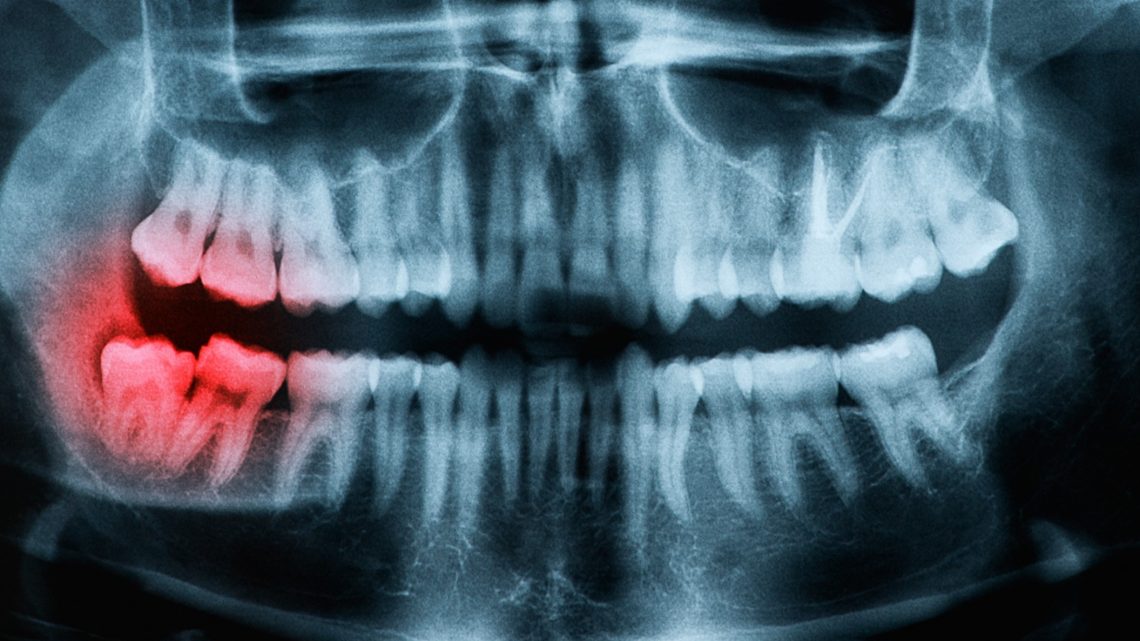

Wisdom teeth have nothing to do with your teeth shifting!

age of teeth and mouth with wisdom teeth

Wisdom teeth (third molars) are the last teeth to grow and often times get impacted due to insufficient space. Many people (including dental professionals) to this day mistakenly believe that the pressure from third molars pushes the rest of the teeth forward causing them to shift. Most research failed to demonstrate an association and more importantly, teeth shift even if wisdom teeth are removed (extracted). For this reason, most orthodontists in the United States do not recommend removal of third molars just to prevent teeth shifting (they should be removed for other reasons however, such as infection, pain, pathology, etc…)